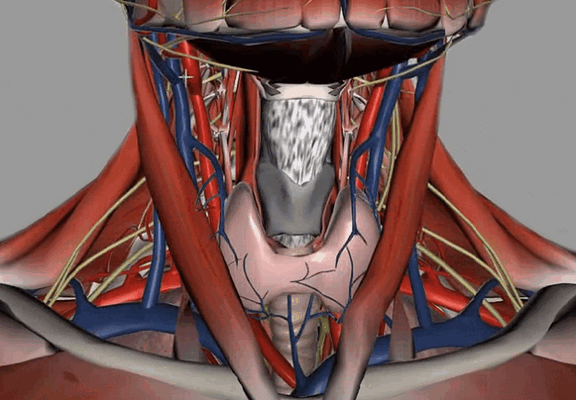

Анатомия шеи

Внутренние структуры зоны интереса

Анатомическая область включает межфасциальные пространства:

пред- и позадиорганное;

Наибольший интерес представляет висцеральное пространство, включающее органы шеи:

глотку с верхней частью пищевода;

гортань и трахею;

пара- и щитовидную железы;

возвратный гортанный нерв.